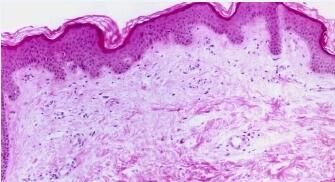

在日常的生活当中荨麻疹属于一种较为多家的皮肤病,也被人们称为风疹团、风疹块,其荨麻疹的种类目前有很多种,其中过敏性荨麻疹就是一种比较多见的荨麻疹,根据观察有很多人对过敏性荨麻疹还不少特别的了解,那么下面我们就一起来了解一下过敏性荨麻疹有哪些症状。

过敏性荨麻疹是多见的皮肤病。急性荨麻疹发病较为缓解,过敏性荨麻疹的突然痒痛,很快呈现大小不等的鲜呈圆形或不规则形,多孤立散在,亦可融合成片。风团可转换为红斑渐渐消失。